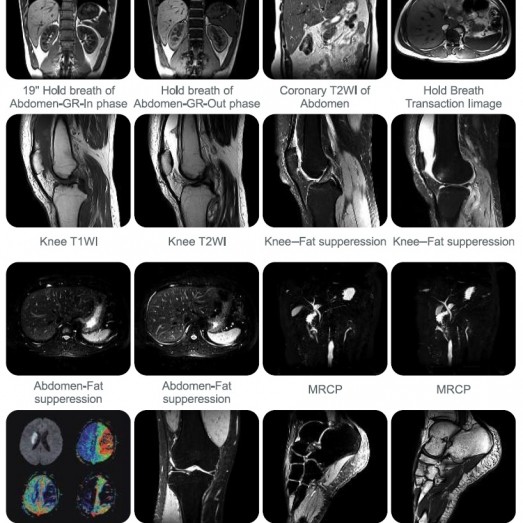

SuperMark 1.5T MRI System

1.5T Zero Consumption Super Condactive Magnet Magnetic Resonance Imaging System